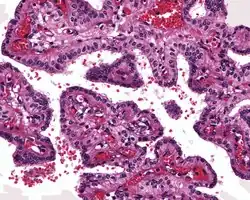

Tumors range from several millimeters up to 10 cm, with larger tumors more frequently seen in older patients. If the tumor is bilateral, it is almost always seen in a VHL patient. The tumor destroys the mastoid air spaces and extends into the middle ear and/or posterior cranial fossa.[1][3]

The microscopic appearance shows an unencapsulated, destructive growth, remodeling and invading bone. The tumor is arranged as simple, broad, non-complex papillary projections without large cystic spaces. The spaces are often fluid filled, have extravasated erythrocytes and/or inspissated material. The cells are cuboidal, usually single layered along the papillary structures, showing indistinct cell borders. The nuclei are round and hyperchromatic.[1][3][10][11]